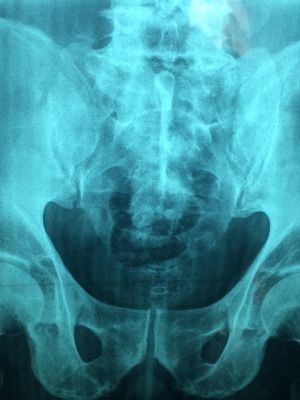

MSCT snimanje karliceMSCT snimanje karlice

Balkan Medic obavlja dijagnostiku putem usluge multislajsni CT skener karlice, koja omogućava detaljan uvid u stanje karličnih organa i kostiju.

Multislajsni CT skener karlice omogućava detaljno snimanje prostora između kukova, gde se nalaze mokraćna bešika, polni organi, limfni čvorovi, delovi creva i koštane strukture karlice. Snimanje se obavlja pomoću rendgenskih zraka i savremene računalne obrade, pri čemu se dobijaju precizni preseci u tankim slojevima. Ovakav prikaz pomaže da se promene jasno uoče i pravilno procene.